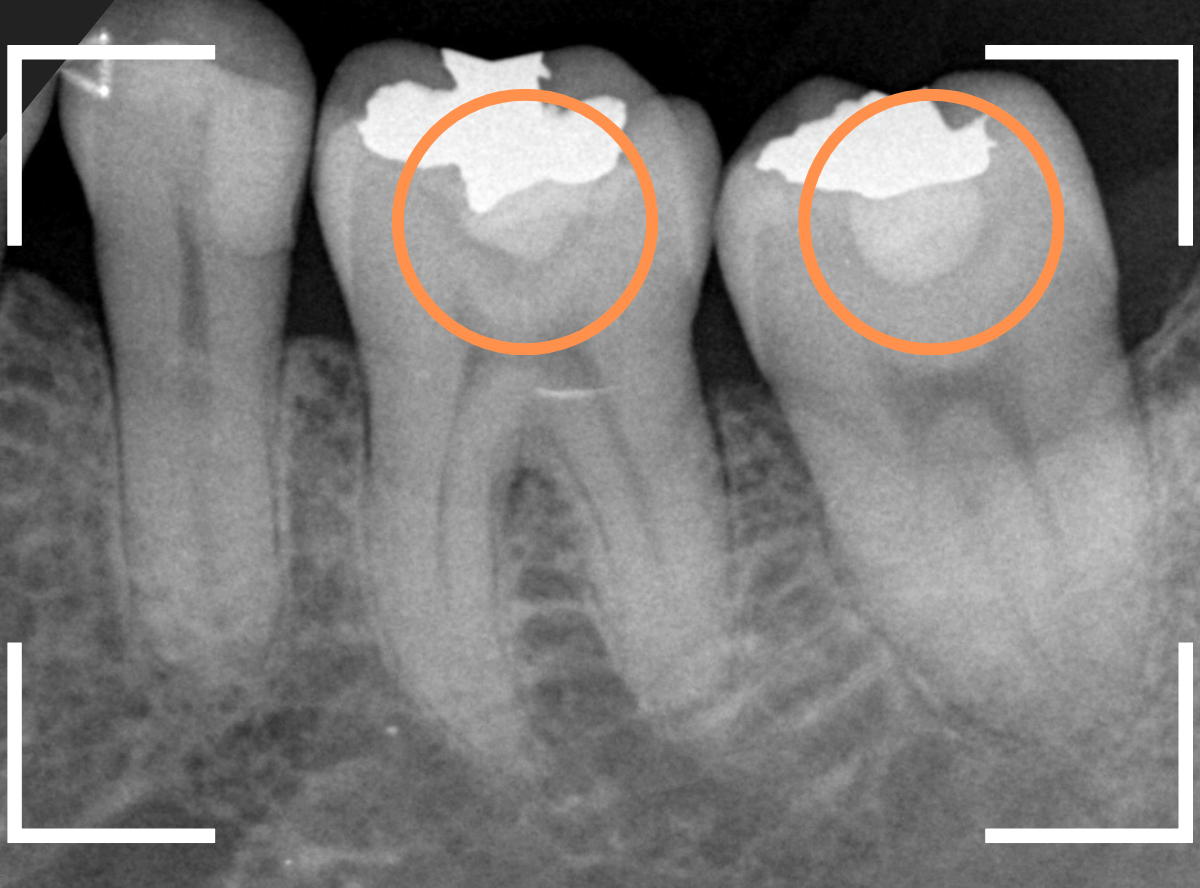

レントゲン写真を撮影しました。

青い線が神経

黄色い線がレジン

赤い線が虫歯

です。

思ったよりも深い虫歯をレジンで埋めてあったようで、さらにその中が虫歯になっている状況です。

神経までかなり近い虫歯と思われます。